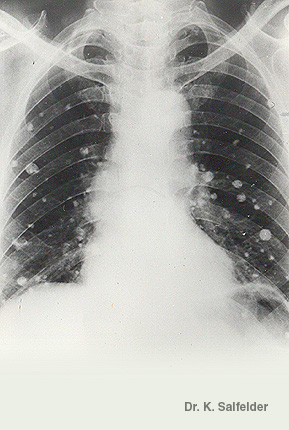

Abb. 9,8: Histoplasmose

Es kommt oft zur Bildung groesserer Herde in den Lungen und zu den sogenannten Histoplasmomen